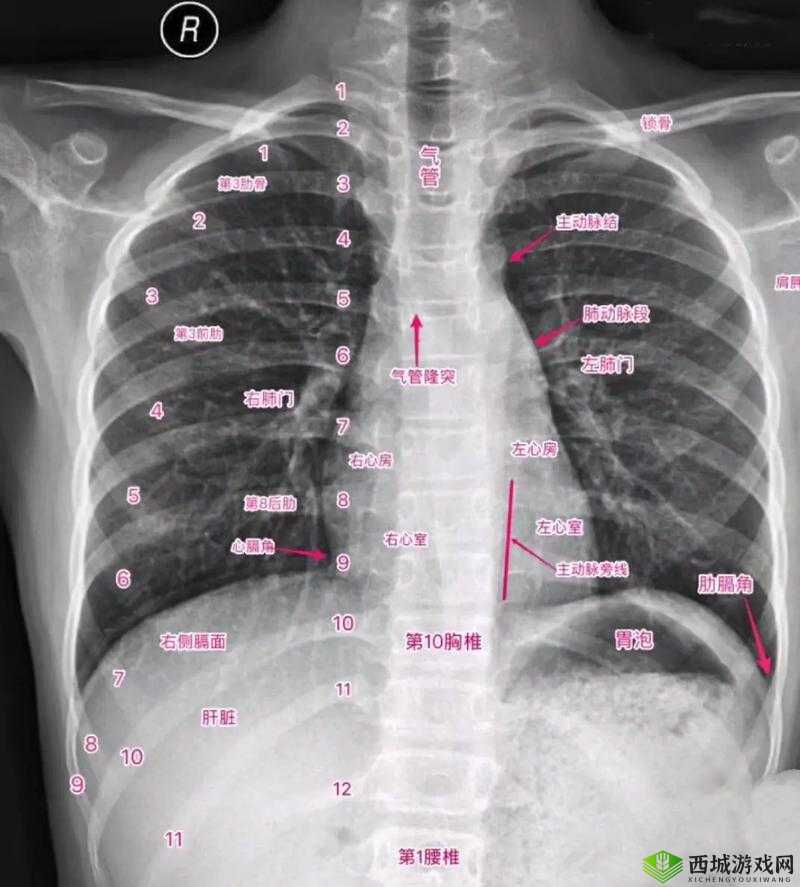

十大曝光胸片:揭示医疗影像背后的不为人知故事

在医疗领域中,胸片是一种常见却又极其重要的检查手段。它就像是一扇神秘的窗户,透过它,我们可以窥探到身体内部的情况。而今天,我们揭开十大曝光胸片背后那些不为人知的故事。

这些曝光的胸片背后,是医生们的精湛医术和敏锐洞察力。他们通过仔细观察和分析每一个细节,从模糊的影像中寻找关键的线索。每一个判断、每一个决策,都关乎着患者的生命和健康。

这些故事也让我们深刻认识到医疗影像技术的重要性。它不仅仅是一种诊断工具,更是拯救生命的关键。没有这些清晰准确的胸片,许多疾病可能会被延误诊断,从而导致不可挽回的后果。